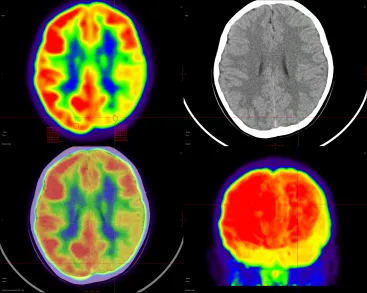

为了明确癫痫病灶,患者家属听从医生建议,带着孩子到前海人寿南宁医院进行PET-CT检查。完成检查后,医院PET-CT结果展示以下表现:

左侧枕叶病灶最明显处SUV最大值为3.939,其放射性摄取与对侧相应部位脑皮质相比降低约25.8%(对侧相应部位SUV最大值为5.106)

左侧颞叶,SUV最大值为3.849,其放射性摄取与对侧相应部位脑皮质相比降低约36.11%(对侧相应部位SUV最大值为5.545)

针对PET-CT呈现的结果,核医学科医生给出了相应的诊断意见:

1.左侧颞叶等FDG代谢明显减低,以左侧颞叶及左下侧颞叶最明显,考虑癫痫灶可能。

2.左侧枕叶等FDG代谢多个局限性放射性摄取明显减低,考虑癫痫灶可能。

18F-FDG PET-CT作为一种无创性的脑代谢及功能显像方法,能够清晰显示解剖结构的同时,可提供大脑生理、代谢等功能信息,进而提高癫痫诊断的灵敏度和准确率。通常情况下,发作期致痫灶区由于神经元细胞异常放电,能量消耗增加,局部脑皮质葡萄糖代谢增高,而发作间期因皮质萎缩、神经元细胞减少及突触活性减低等各种原因,脑皮质葡萄糖代谢减低。研究显示,PET-CT对癫痫灶检出率约为80%~90%,如通过定量分析,检出率可超过90%,即使是针对MRI阴性的癫痫,18F-FDG PET显像仍可以进一步准确定位80%的患者。同时,将18F-FDG PET图像与MRI图像进行融合更有助于发现隐匿性、局灶性发育不良病灶,增加患者和医生对手术治疗的信心,影响手术决策。